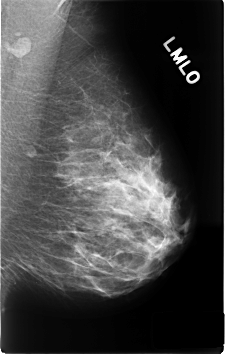

C_0339_1.LEFT_MLO

LEFT_MLO LINES 4592 PIXELS_PER_LINE 2920 BITS_PER_PIXEL 12 RESOLUTION 50 NON_OVERLAY